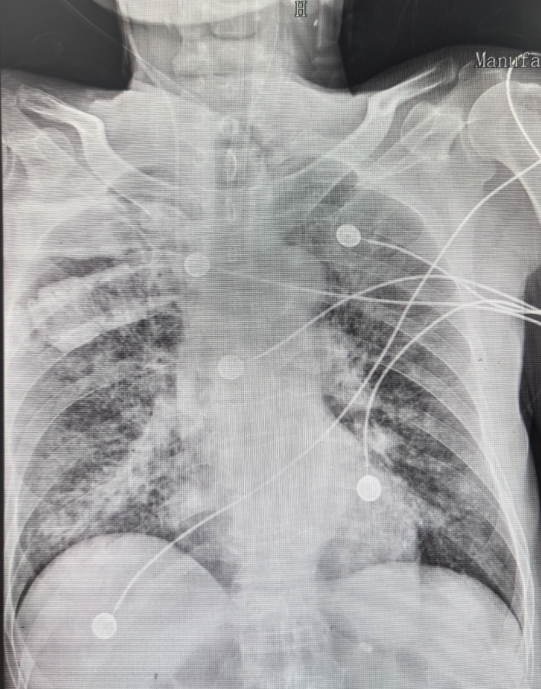

现病史: 患者12月26日被家人发现无诱因出现呼吸困难、全身湿冷, 伴咳嗽咳痰, 黄痰。测体温不高, 遂就诊于我院急诊科。床旁胸片示双肺多发片状阴影(1)血气分析示Ⅰ型呼吸衰竭, 测血压80/45mmHg; 立即予无创通气、多巴胺持续泵入、抗感染等治疗后收入我科。

图片

1  患者急诊+胸部X线片